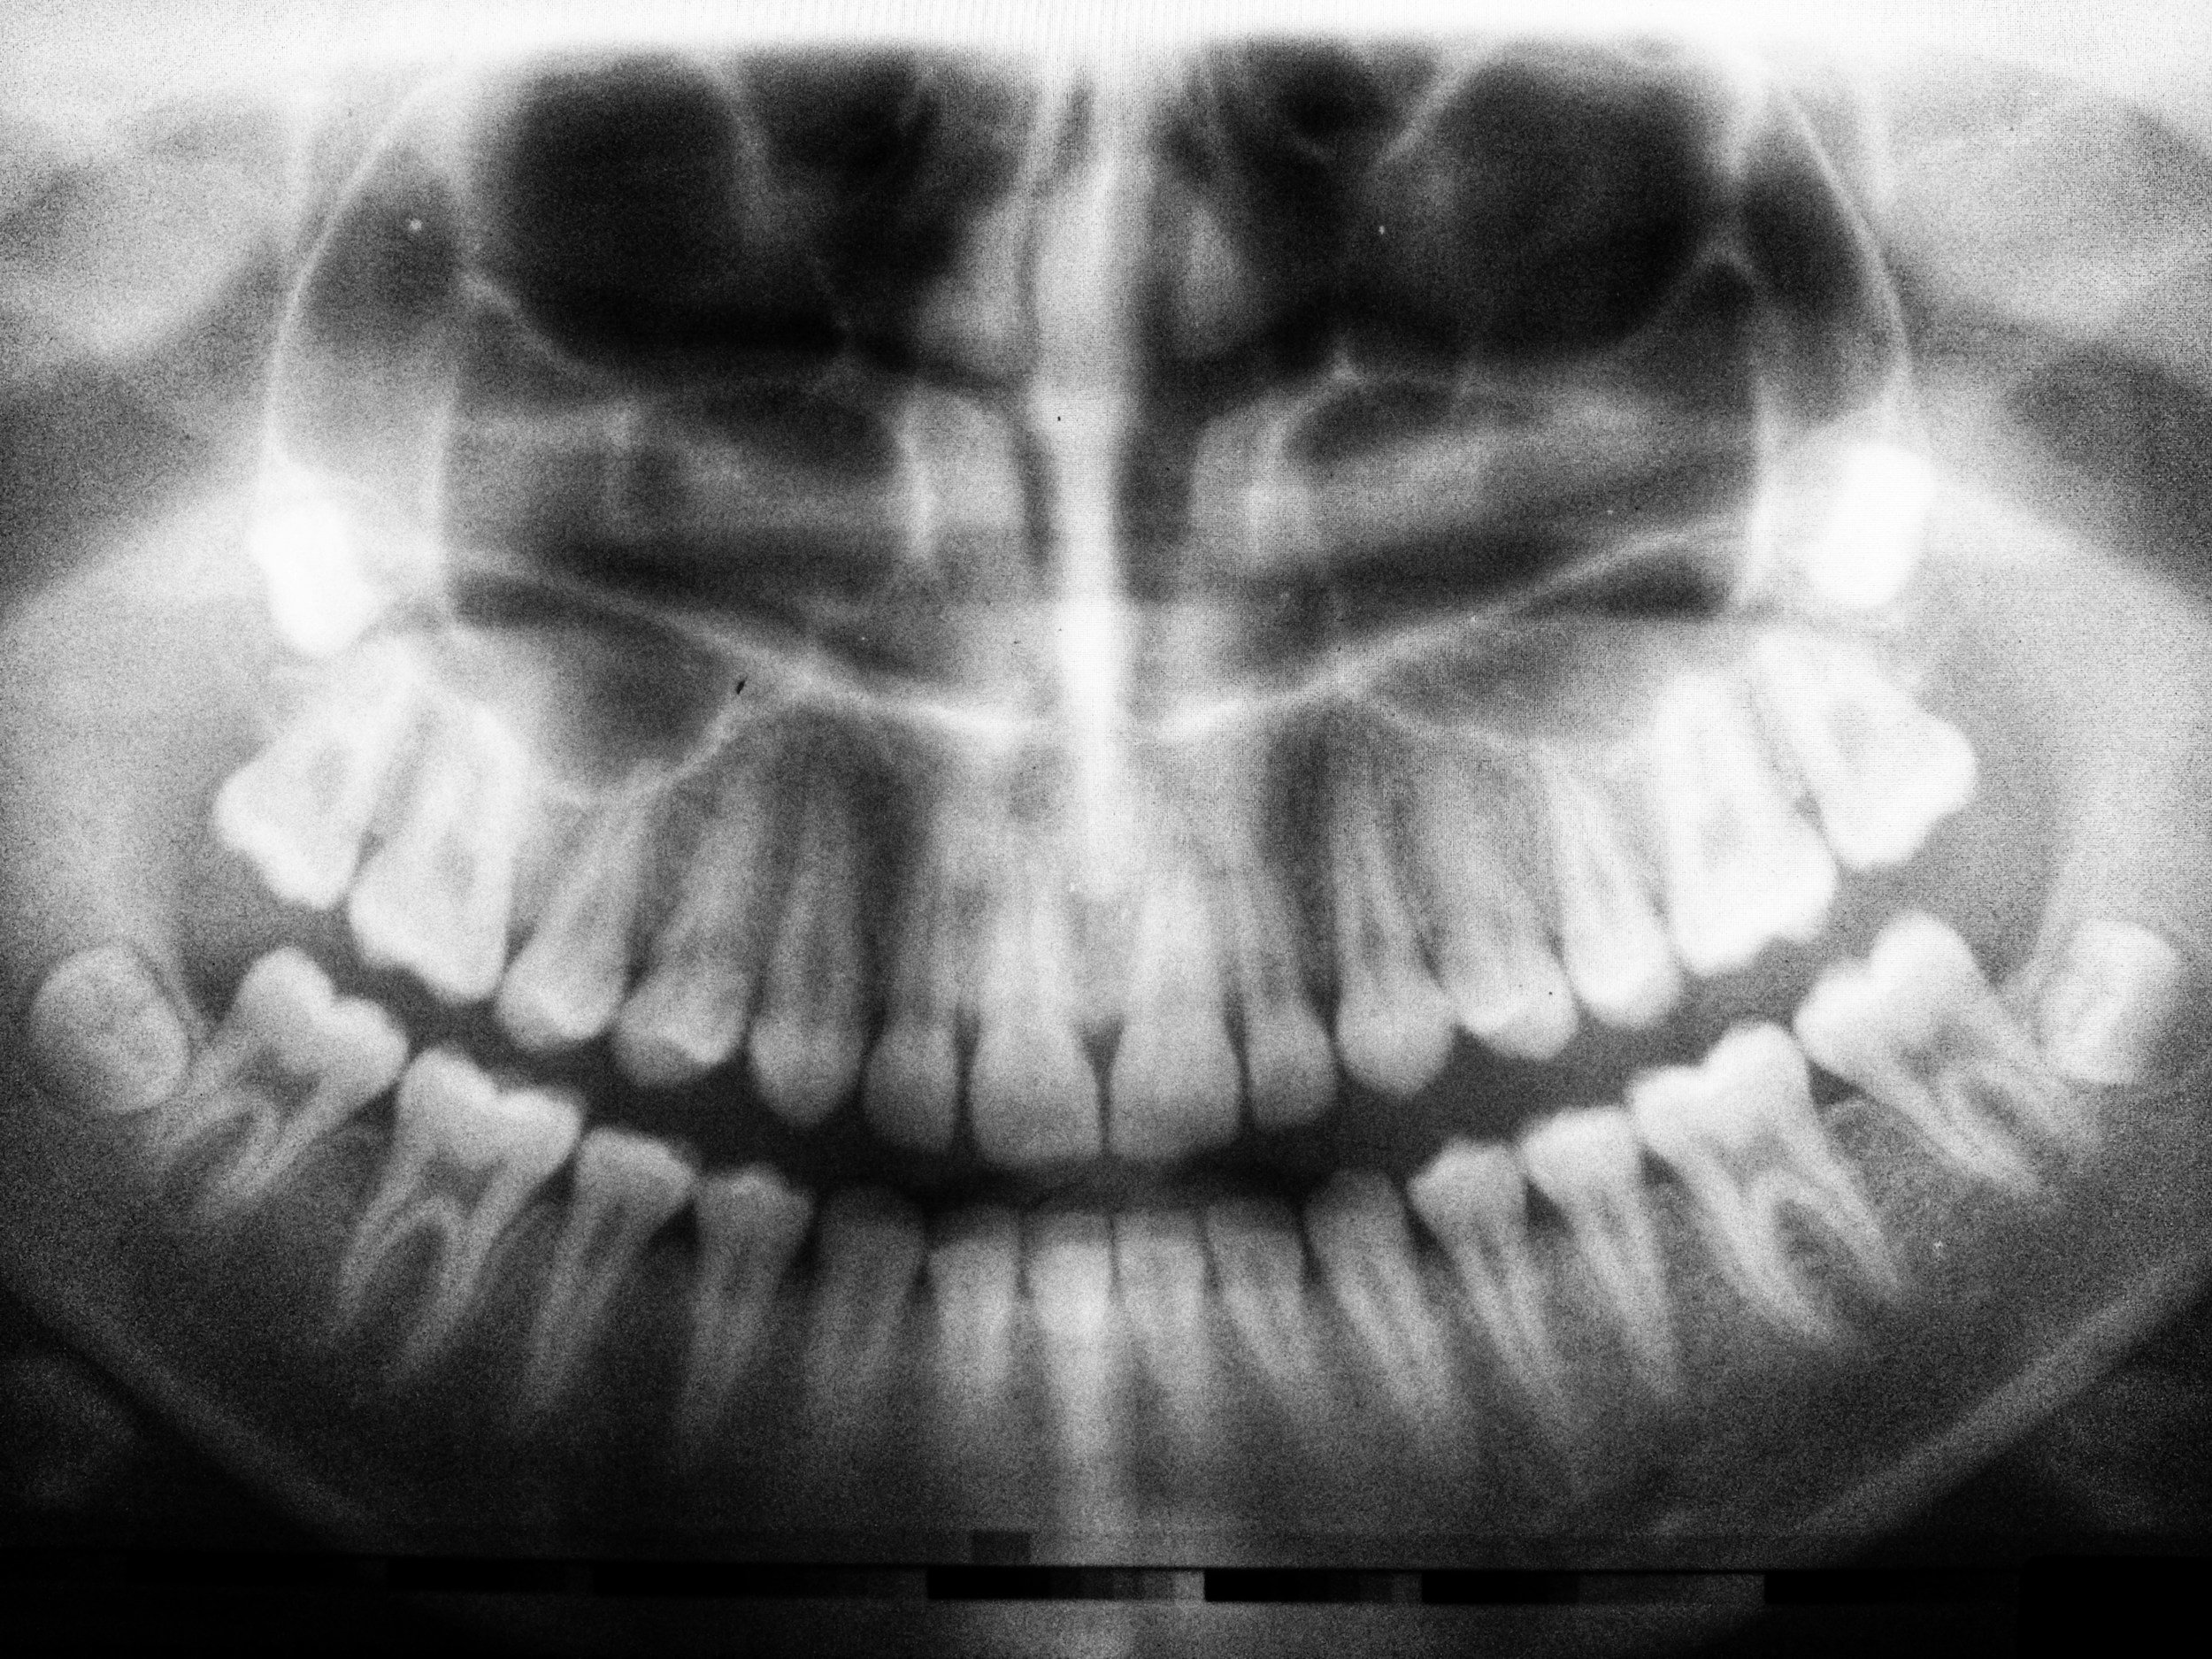

Digital x-rays are quickly becoming adopted by a large percentage of the dental industry. A digital x-ray allows the dentist to take an image of the tooth or teeth and put it into an imaging program. Within this imaging program, there are a number of tools that will allow the dentist to take a very close look at the teeth and surrounding structures with amazing accuracy. As a benefit to the patient, the digital x-ray also provides nearly 80% less radiation than a standard x-ray. This is due to the fact that the digital version of the x-ray is much more sensitive to this radiation and has been specifically designed with the patient in mind.